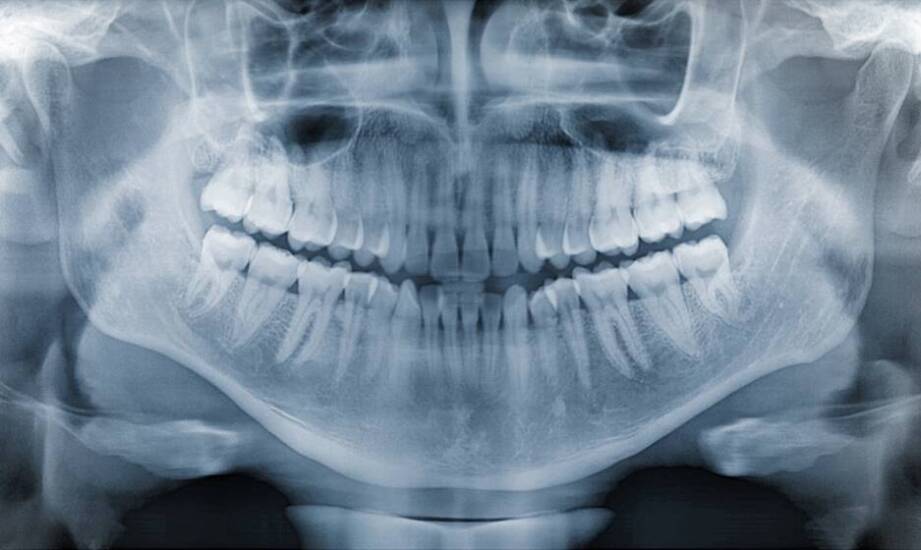

Tomografia komputerowa to narzędzie w diagnostyce stomatologicznej, które wspiera postępowanie diagnostyczne u pacjentów. Dzięki obrazowaniu struktur zębowych oraz otaczających tkanek specjaliści mogą ocenić stan jamy ustnej i zaplanować dalsze działania. Technologia ta bywa wykorzystywana w bardziej złożonych przypadkach, takich jak choroby przyzębia czy niewłaściwie umiejscowione zęby mądrości. Tomografia komputerowa znajduje również zastosowanie w ortodoncji oraz implantologii, gdzie obrazowanie trójwymiarowe ma znaczenie w planowaniu postępowania.

Tomografia komputerowa ma na celu wsparcie w skomplikowanych przypadkach diagnostycznych. Stosuje się ją w ocenie stanu kości, zębów oraz tkanek miękkich. Trójwymiarowe obrazy umożliwiają lekarzom dokładniejsze planowanie postępowania, co dotyczy endodoncji oraz chirurgii stomatologicznej. Może być wykonana, gdy inne metody obrazowania, takie jak zdjęcia rentgenowskie, nie dostarczają wystarczających informacji. Przykładem może być podejrzenie złamania korony lub korzenia zęba, które wymaga dokładnej oceny. Inną sytuacją jest konieczność usunięcia zęba mądrości, zwłaszcza gdy korzeń jest zakrzywiony lub znajduje się blisko nerwu. Tomografia może ułatwić ocenę relacji anatomicznych przed zabiegiem i wspierać planowanie postępowania. W przypadku leczenia kanałowego również może być niezbędna, gdy istnieje trudność w odnalezieniu kanałów korzeniowych lub podejrzenie zmian w tkankach otaczających ząb. W takich sytuacjach możliwa jest konsultacja z dentystą w Łodzi, w celu omówienia wskazań do usługi tomografii komputerowej oraz dalszego postępowania diagnostyczno-terapeutycznego.

Zastosowanie tomografii komputerowej w stomatologii ma na celu zwiększenie precyzji diagnozy, co pozwala na dokładniejsze określenie problemu i lepsze zaplanowanie kolejnych etapów postępowania. Dzięki temu specjaliści mogą lepiej planować leczenie, co może mieć znaczenie dla doboru metod i kolejności działań. Tomografia komputerowa może także wspierać ocenę ryzyka związanego z planowanym zabiegiem, ponieważ umożliwia zobrazowanie struktur anatomicznych i identyfikację ewentualnych przeciwwskazań do przeprowadzenia danego zabiegu. Stomatologia Podbiałowa Olgi Lindorf-Guzek oferuje usługi tomografii komputerowej w ramach diagnostyki stomatologicznej, co pozwala uzyskać informacje o stanie jamy ustnej potrzebne do oceny klinicznej. W praktyce diagnostycznej takie obrazowanie bywa wykorzystywane również do dokumentacji oraz do porównania zmian w czasie, zależnie od wskazań i decyzji lekarza prowadzącego.